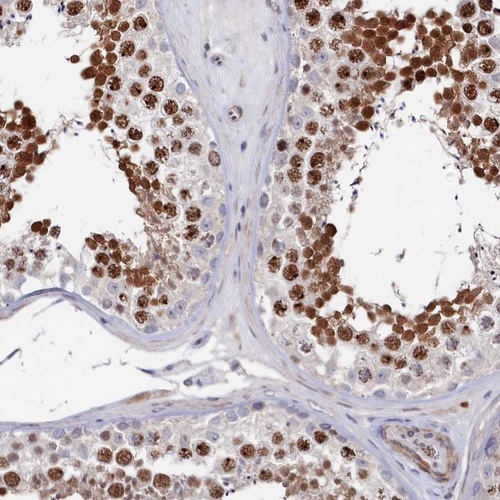

Immunohistochemical staining of human testis shows strong nuclear positivity in cells in seminiferus ducts.